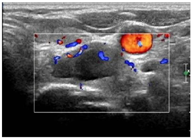

入院后行甲状腺超声示甲状腺左叶上、下极深方甲状旁腺区见2个囊实性结节,大小分别为2.9cm×1.4cm×1.1cm、2.3cm×1.4cm×1.2cm,均形态规则,边界清晰,CDFI:内见较丰富血流信号(图1,图2,图3,图4)。行甲状旁腺融合显像(显像剂:99Tcm-MIBI)示甲状腺左叶上极后上方见结节样显像剂浓聚灶,相应CT层面示椭圆形软组织密度影,边界清,大小约27.6mm×18.2mm×16.0mm。CT另见甲状腺左叶下极后下方一椭圆形软组织密度影,边界较清,大小约25mm×13.7mm×12.5mm,相应ECT层面未见显像剂摄取(图5,图6)。行嗜铬细胞瘤融合成像(显像剂:131I-MIBG)示颈部及腹部可见显像剂摄取病灶(图7,图8)。

超声图像中左侧甲状旁腺区2枚囊实性结节形态、回声、位置及血流均相似,结合实验室检查及临床病史,均提示为甲状旁腺腺瘤,但甲状旁腺融合成像仅支持甲状腺左叶上极后方结节为甲状旁腺腺瘤。甲状腺左叶下极后方结节无99Tcm-MIBI显像剂摄取,但有131I-MIBG高摄取,故综合以上考虑甲状腺左叶上极后方结节为甲状旁腺腺瘤,左叶下极后方结节为副神经节瘤。

充分告知患者及家属治疗目的、手段及可能出现的并发症后患者签署知情同意书,完成凝血功能化验、心电图、喉镜等数前评估。术前禁食4h,建立静脉通道,术前sonovue超声造影(CEUS)示甲状腺旁腺腺瘤结节与甲状腺实质同步增强,呈不均匀等增强(图9,视频1)。患者呈仰卧位,充分暴露颈部,常规消毒铺巾,消融后1%利多卡因局部麻醉,甲状旁腺结节后缘注射5~10ml生理盐水形成隔离带(视频2、3),以保护周围血管、气管、食管、喉返神经等正常组织。将16G微波消融针置于病变中央,输出功率为30W,消融后气泡样强回声较多时及时更换位置,直至强回声完全覆盖病灶时停止操作,共计1分20秒(图10,视频4、5)。消融后行CEUS评估,评估甲状旁腺病灶内未见造影剂进入(图11,视频6)。消融结束后,消融区域压迫30分钟,并观察2h。术中及术后观察均未发现出血、声音嘶哑等并发症。